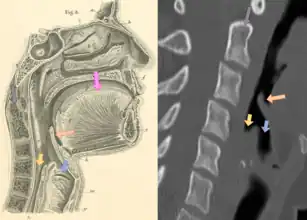

![]() | |

| Neck X-ray showing thumbprint sign. | |

Epiglottitis was historically mostly caused by infection by H. influenzae type b (commonly referred to as "Hib").[1] With vaccination, it is now more often caused by other bacteria, most commonly Streptococcus pneumoniae, Streptococcus pyogenes, or Staphylococcus aureus.[1] Predisposing factors include burns and trauma to the area.[1] The most accurate way to make the diagnosis is to look directly at the epiglottis.[3] X-rays of the neck from the side may show a "thumbprint sign" but the lack of this sign does not mean the condition is absent.[1]

On lateral C-spine X-ray, the thumbprint sign describes a swollen, enlarged epiglottis.[10] A normal X-ray, however, does not exclude the diagnosis.[10] An ultrasound may be helpful if specific changes are present, but its use (as of 2018) is in the early stages of study.[10]